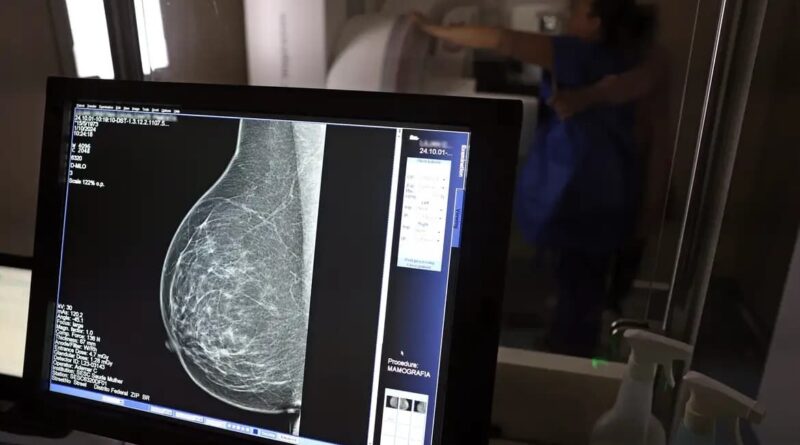

Câncer de mama segue como principal causa de morte por neoplasias entre mulheres na Bahia, diz levantamento

Em Salvador, essa taxa foi ainda mais elevada: 64,3 casos por 100 mil soteropolitanas.